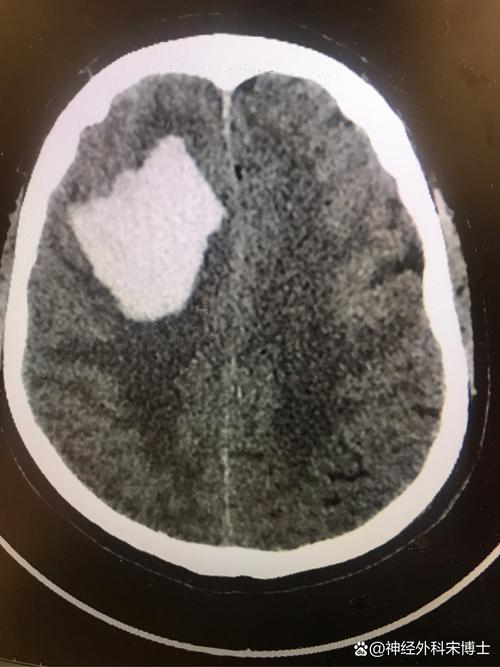

(图片来源网络,侵删)

什么是“左脑小面积脑梗”?

- 脑梗(缺血性脑卒中):通俗地说,就是大脑的某一部分血管被堵塞了,导致该区域的脑组织因为缺血缺氧而坏死。

- 小面积:意味着堵塞的血管不是主要的“大动脉”(如大脑中动脉),而是其分支较小的血管,坏死的脑组织范围有限,对整体功能的影响相对较小,治疗和恢复的潜力也更大。